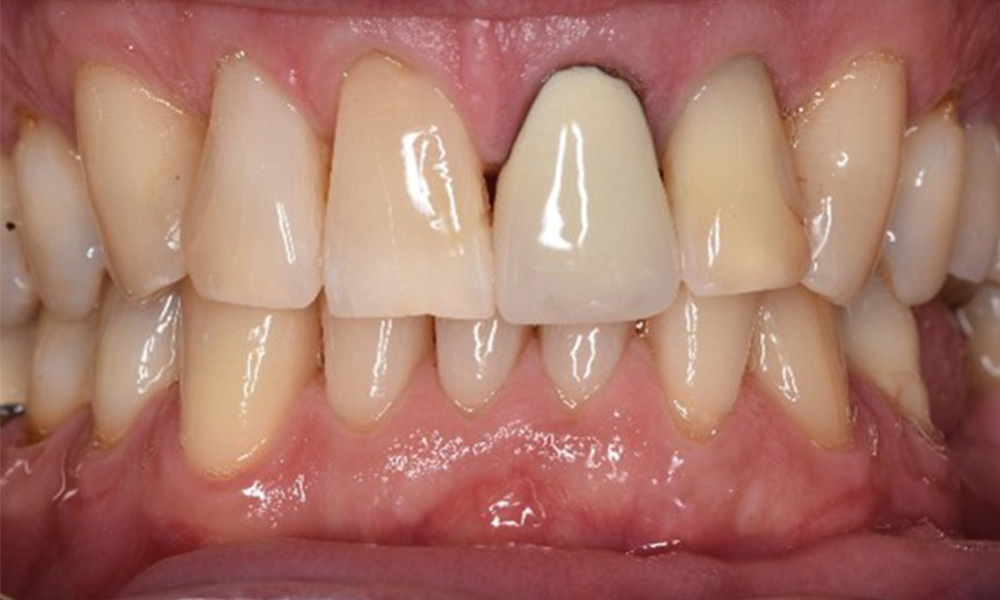

Frontansicht Gebiss (Ober- und Unterkiefer)

Frontansicht

Der Patient hat einige zahnärztliche Restaurationen und zwei Implantate (2. und 4. Quadrant). Anhand der aktuellen Befunde lässt sich eine Gingivitis bei stabilem parodontalen Zustand am reduzierten Parodont (Stadium III, Grad A) feststellen.